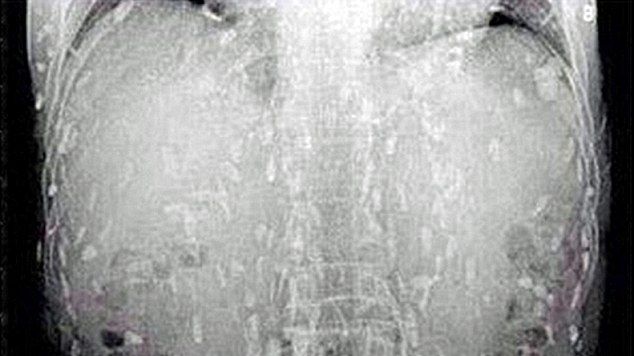

Potrivit Daily Mail, bărbatul s-a dus la medic, inițial, acuzând dureri de stomac și o iritație pe piele. La o simplă radiografie, medicii și-au dat seama că trupul omului este infectat cu viermi din cauza mâncării contaminate.